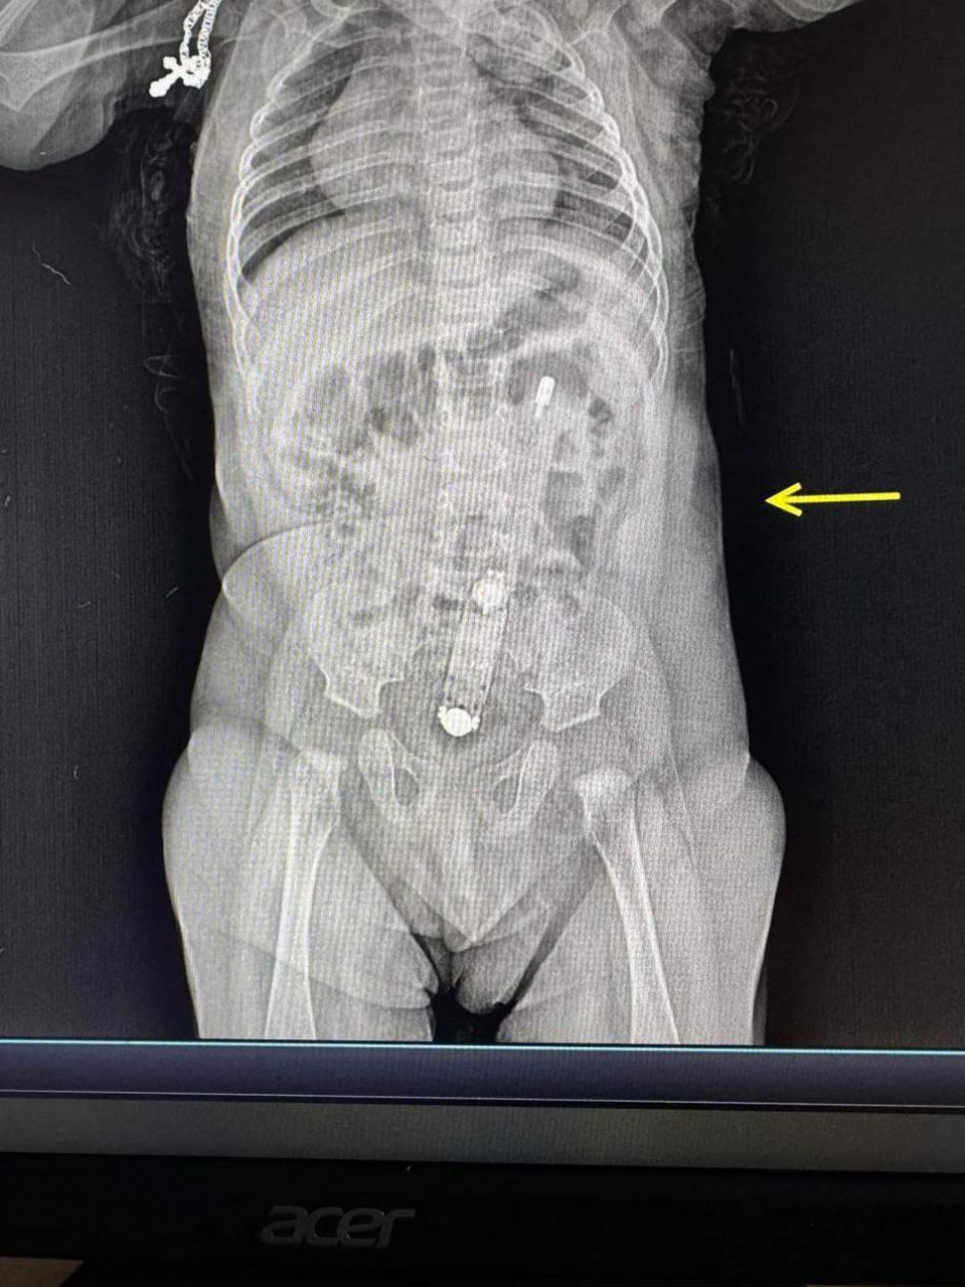

На рентгене было четко видно термометр, также он пальпировался через живот. "Достать прибор было очень непросто", - рассказывает хирург и эндоскопистка Юлия Артышук.

"Сделали это эндоскопически. Действовать надо было очень осторожно, чтобы не травмировать младенцу анус и внутренние органы. Самостоятельно градусник выйти не мог, зато мог перфорировать кишечник или в дальнейшем спровоцировать кишечную непроходимость", - сказала она.